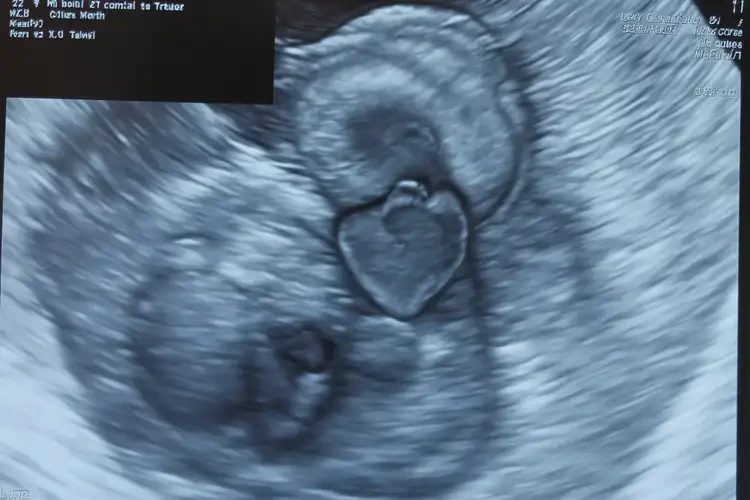

孕22周2天胎心92怎么回事

胎心92次/分鐘

孕22周2天時,胎兒的正常胎心率范圍應在120-160次/分鐘。胎心92次/分鐘明顯低于正常范圍,可能提示存在某些問題,需要引起重視。以下是可能的原因和應對措施:

孕22周2天胎心92怎么回事(圖1)